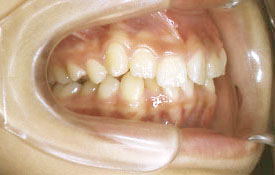

インビザラインの治療例:CASE-2

| プロフィール | 15歳 男性 |

| 所見 | アメリカから転院されて来られた方です。 インビザラインで上下顎の矯正治療を開始し下顎はアメリカで終了しており、上顎のみ治療の後期を担当しました。 アイライナーの装着は、1日平均22時間ほどでした。 |